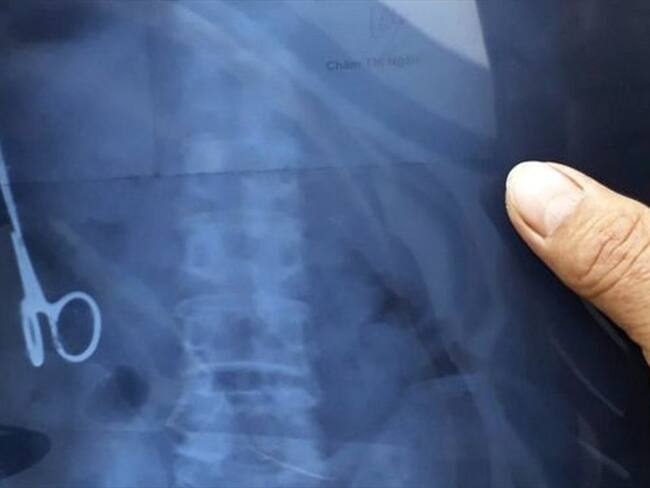

Un ultrasonido mostró que Ma Van Nhat vivía con una tijera en el estómago.. Foto: BBC Mundo(Thot)